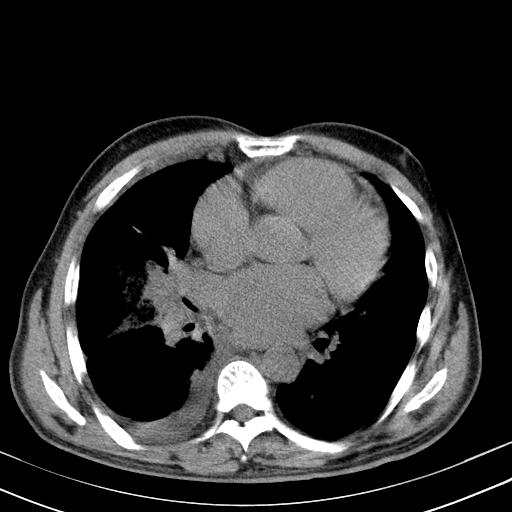

以下是引用zxl51642在2010-3-21 17:06:00的发言:[br]右下中心型肺癌并阻塞性肺炎/不张,纵膈淋巴结肿大,右侧大量胸腔积液,左侧少量胸腔积液,少量腹水。建议纤维支气管镜进一步检查。